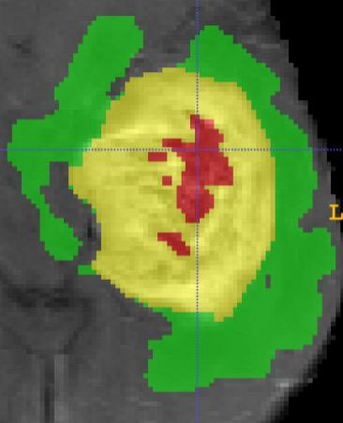

As information sources are usually imperfect, it is necessary to take into account their reliability in multi-source information fusion tasks. In this paper, we propose a new deep framework allowing us to merge multi-MR image segmentation results using the formalism of Dempster-Shafer theory while taking into account the reliability of different modalities relative to different classes. The framework is composed of an encoder-decoder feature extraction module, an evidential segmentation module that computes a belief function at each voxel for each modality, and a multi-modality evidence fusion module, which assigns a vector of discount rates to each modality evidence and combines the discounted evidence using Dempster's rule. The whole framework is trained by minimizing a new loss function based on a discounted Dice index to increase segmentation accuracy and reliability. The method was evaluated on the BraTs 2021 database of 1251 patients with brain tumors. Quantitative and qualitative results show that our method outperforms the state of the art, and implements an effective new idea for merging multi-information within deep neural networks.